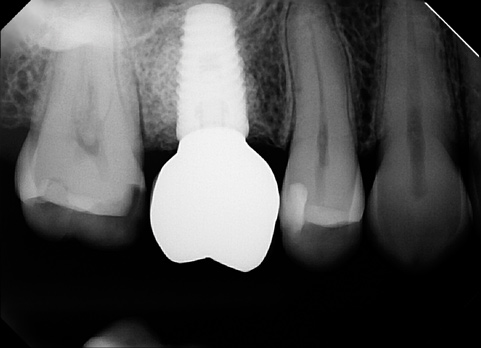

(15.) Clinical photograph at 36 months posttreatment, demonstrating stability of the gingival margin and absence of gingival inflammation around the restoration.

Figure 15